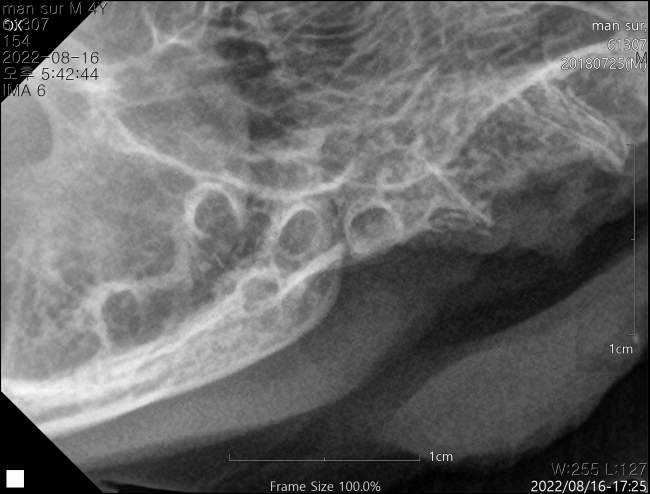

치료중 대상묘

안녕하세요 제가 돌보는 길냥이 전발치 후에도 염증이 심한데 가라앉는데 기간이 얼마나 소요 되셨을까요?ㅜㅜ